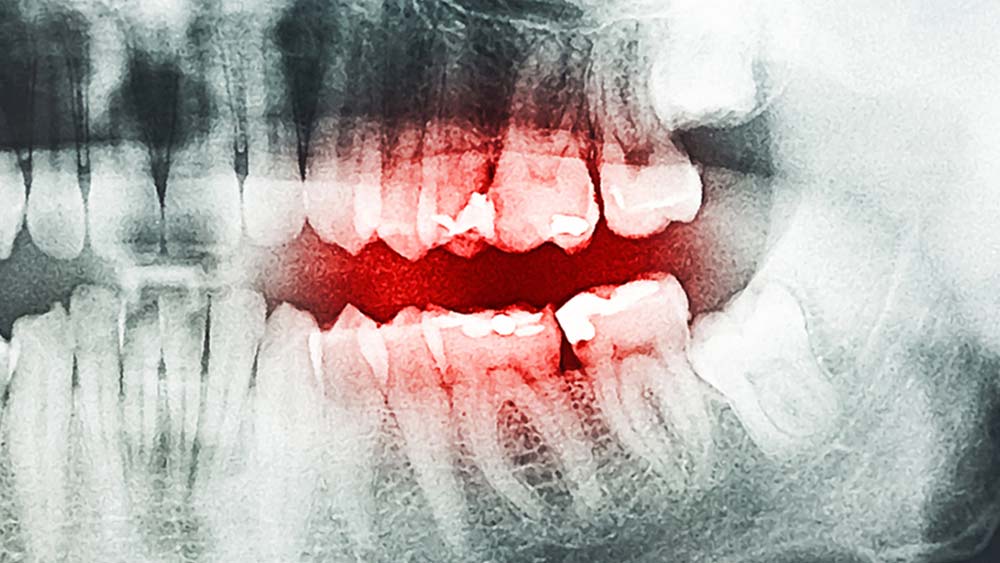

Ursachen für einen „falschen Biss“ können unter anderem gekippte oder fehlende Zähne, zu hohe Zahnfüllungen oder schlecht sitzender Zahnersatz sein. Da das System aus Zähnen, Kiefergelenken, Muskeln und Nerven sehr sensibel ist, können bereits leichte Störungen Probleme bereiten.